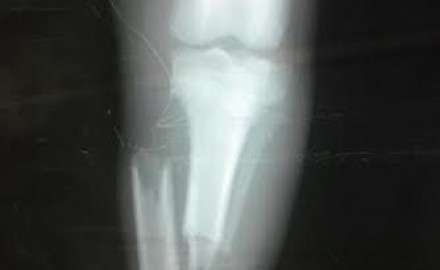

Zilnic primim zeci de telefoane in care ni se relateaza diferite situatii si mai ales ni se cere ajutorul, dar acest telefon ne-a facut sa nu avem somn si liniste. Un mecanic de locomotiva ne spune ca langa calea ferata pe unde trece cu trenul pe care il conduce,zace un catel de...